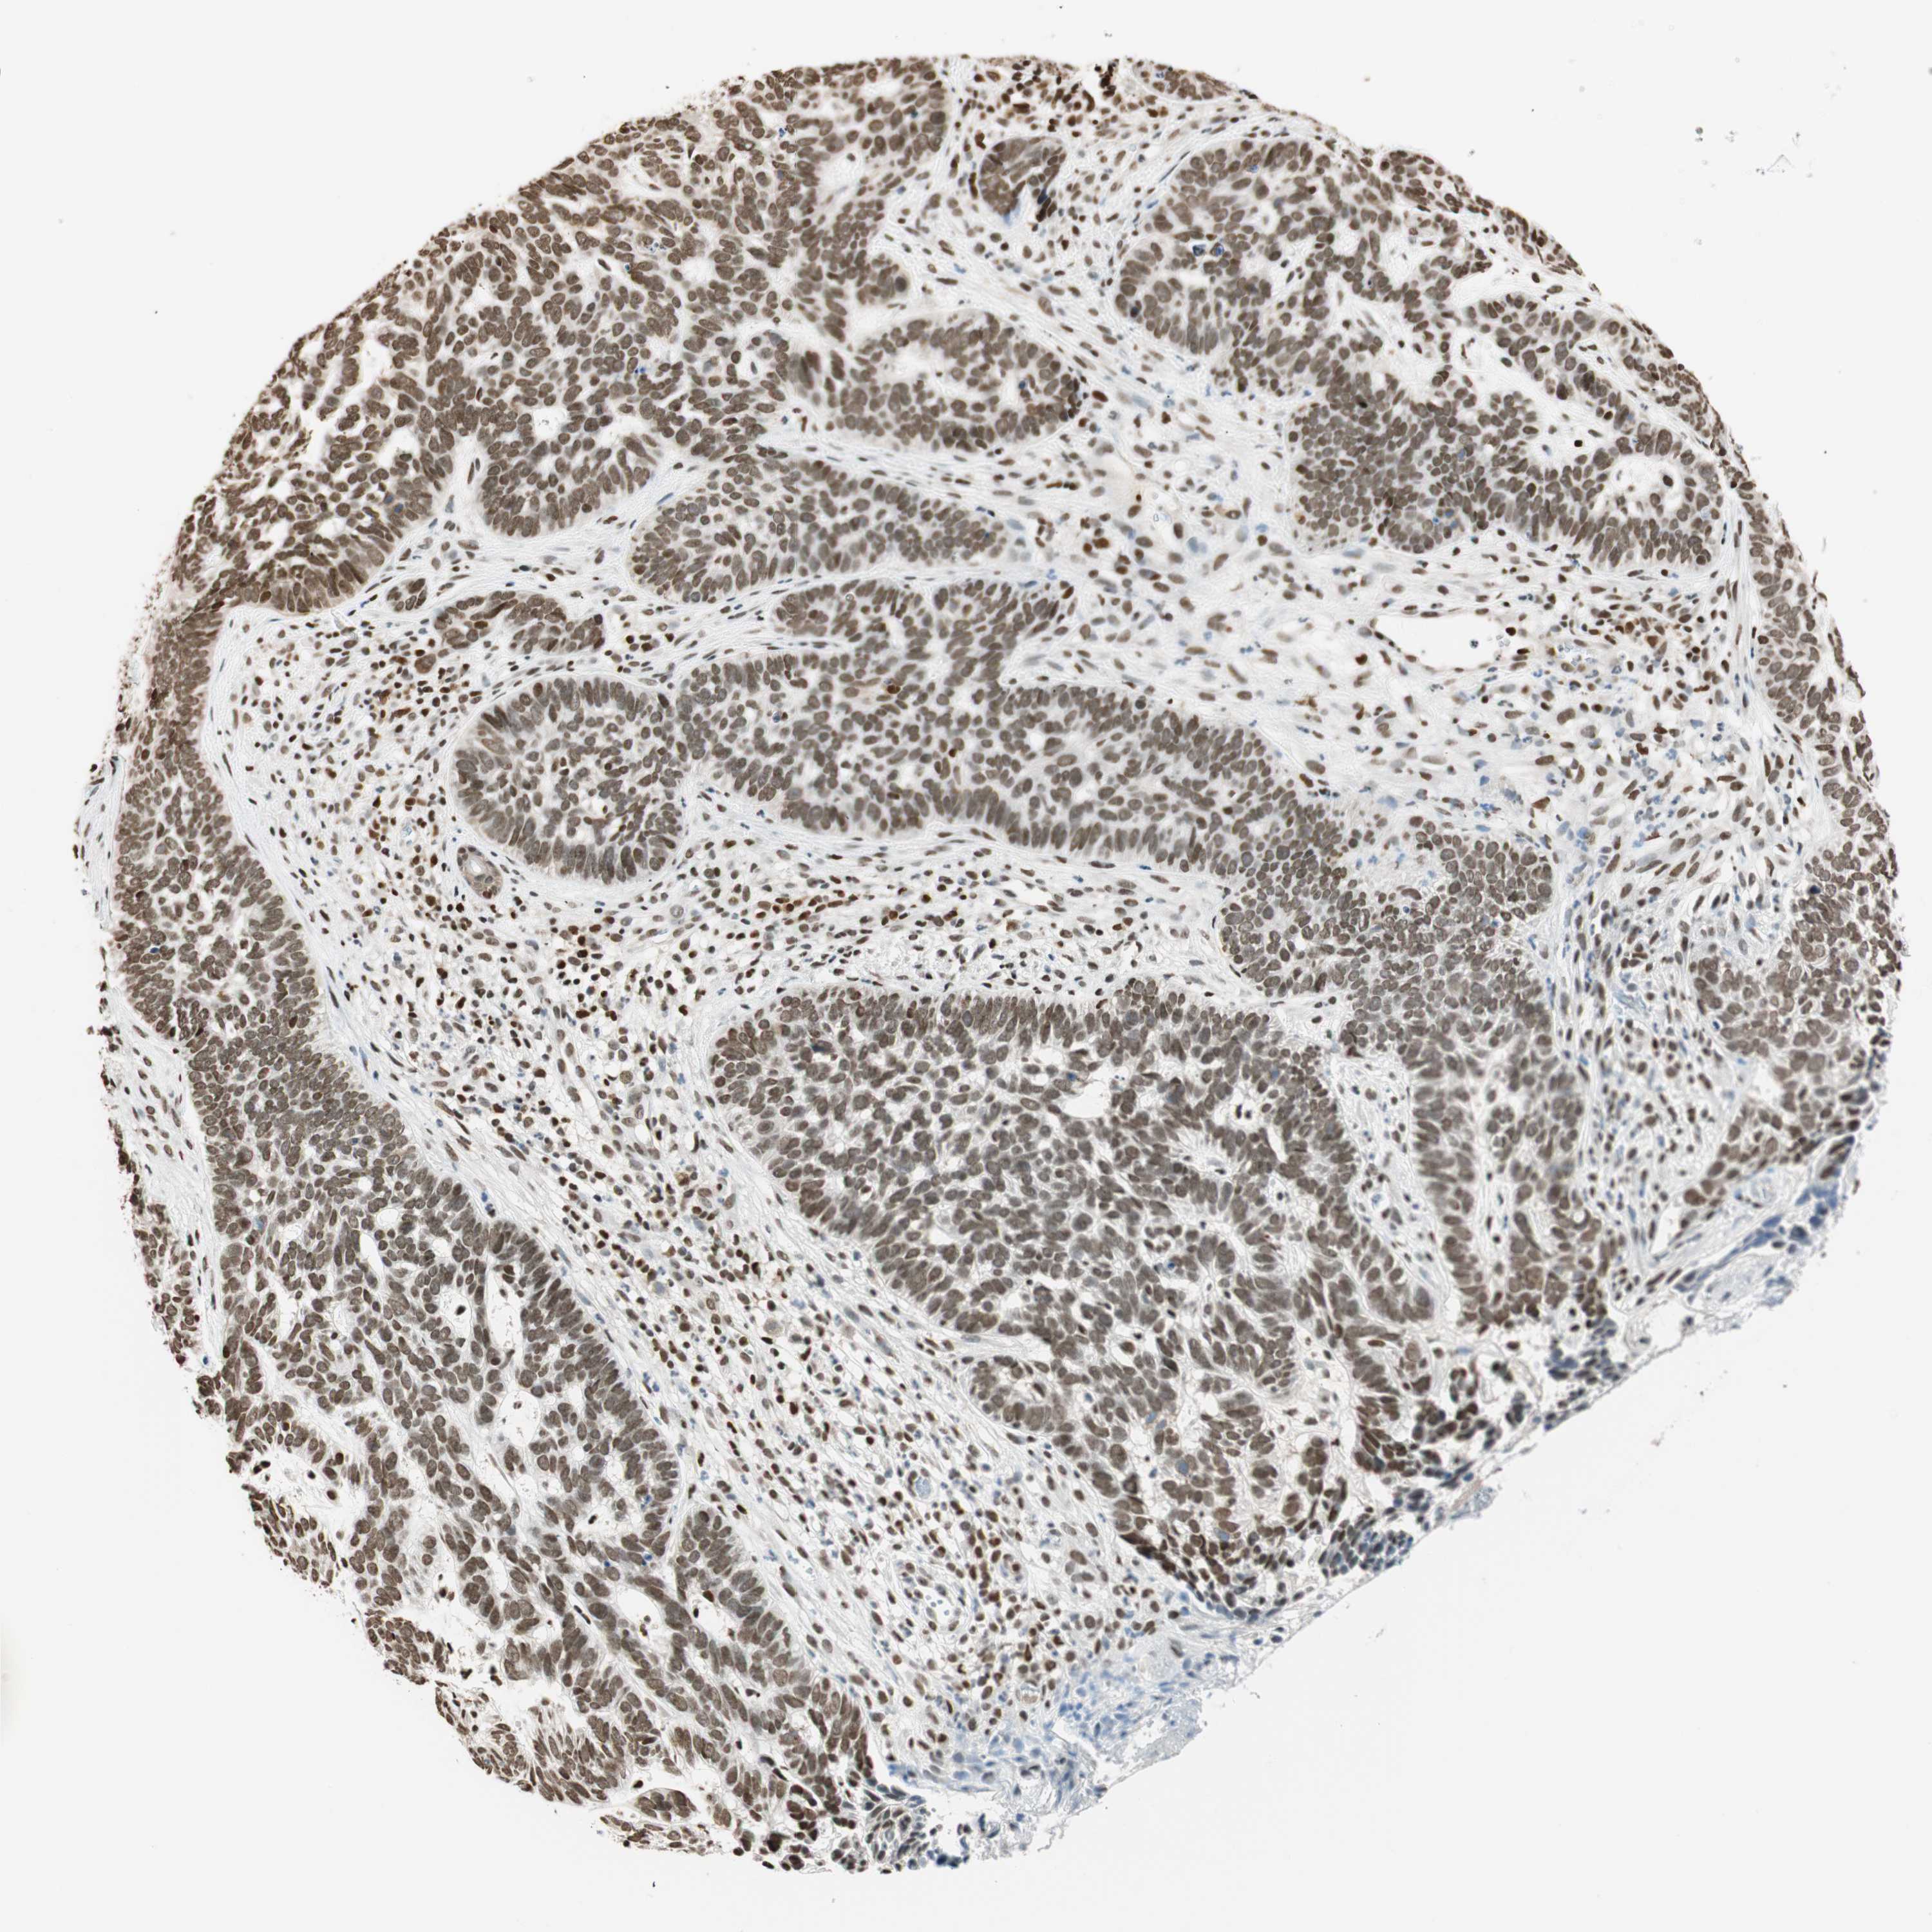

SKIN CANCER - Protein expressioni

A mouse-over function shows sample information and annotation data. Click on an image to view it in a full screen mode. Samples can be filtered based on level of antibody staining by selecting one or several of the following categories: high, medium, low and not detected. The assay and annotation is described here.

Antibody stainingi

Antibody staining in the annotated cell types in the current human tissue is reported as not detected, low, medium, or high, based on conventional immunohistochemistry profiling in selected tissues. This score is based on the combination of the staining intensity and fraction of stained cells.

Each image is clickable and will lead to virtual microscopy that enables deeper exploration of all samples and also displays staining intensity scores, fraction scores and subcellular localization as well as patient and tissue information for each sample.

Antibody CAB008105

Staining

High

Medium

Low

Not detected

Intensity

Strong

Moderate

Weak

Negative

Quantity

>75%

75%-25%

<25%

None

Location

Nuclear

Cytoplasmic/membranous

Cytoplasmic/membranous,nuclear

Squamous cell carcinoma, NOS

Squamous cell carcinoma, metastatic, NOS

Basal cell carcinoma